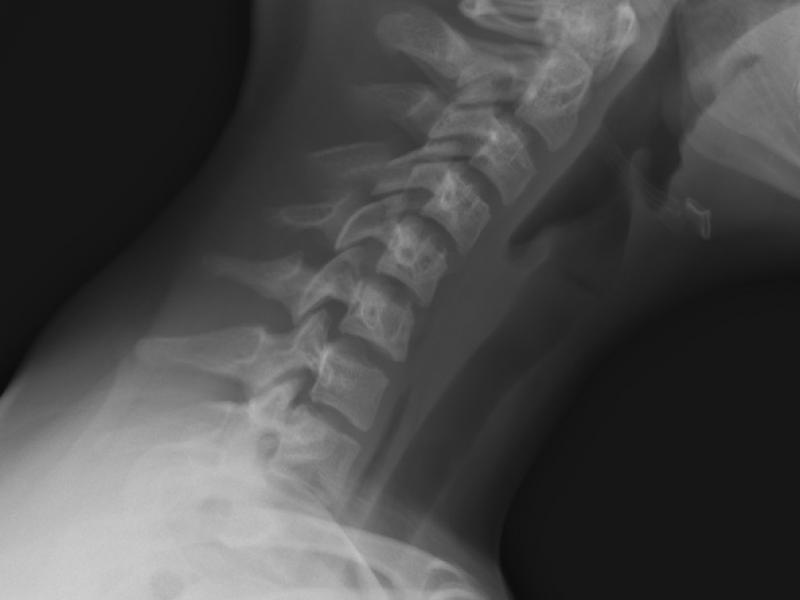

A 14 yo female c/o neck pain in the ED, no radicular

What's the Diagnosis?